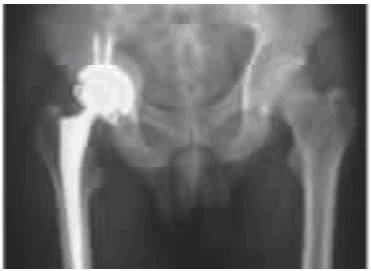

图5 术后2个月X线片示假体位置良好

应用抗生素治疗6周后,复查超敏C反应蛋白3.02mg/L,血沉19mm/h。考虑患者对肢体功能要求高、手术意愿强烈,于全麻下行右侧全髋关节置换术(total hip arthroplasty,THA)。术中见髋臼侧较大骨缺损,向髋臼内打压植入同种异体骨,安装直径58mm生物型髋臼假体、植入2枚30mm螺钉,安装12号Corail标准生物型股骨柄,选用同型36mm、12/14、+1.5mm股骨头及10度限制性高交联聚乙烯内衬。复位后髋关节在各个方向活动度良好。术后严禁髋关节内收、内旋,指导患者锻炼股四头肌、臀中肌等肌肉力量,2个月内避免右下肢完全负重。术后2个月X线片示人工关节位置良好,无松动或折断(见图5)。术后1年随访右髋关节功能良好,关节活动度基本正常,无不适主诉。